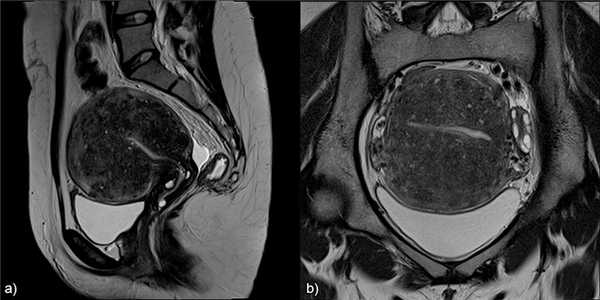

![]()

Рис.4: Диффузный аденомиоз: а) сагиттальные и b) корональные T2 изображения, показывающие утолщение переходной зоны c образованием плохо отграниченной области с низкой интенсивностью сигнала, точечными гиперинтенсивными включениями.

Рис.5: Фокальный аденомиоз: а) сагиттальные T2, b) аксиальные T2 , с) аксиальные T1 3D FS изображения, показывающие фокальное асимметричное утолщение переходной зоны, образующее плохо отграниченную область с низкой интенсивностью сигнала, наличием в структуре мелких гиперинтенсивных на Т2 и Т1FS включений, представленных мелкими кровоизлияниями.